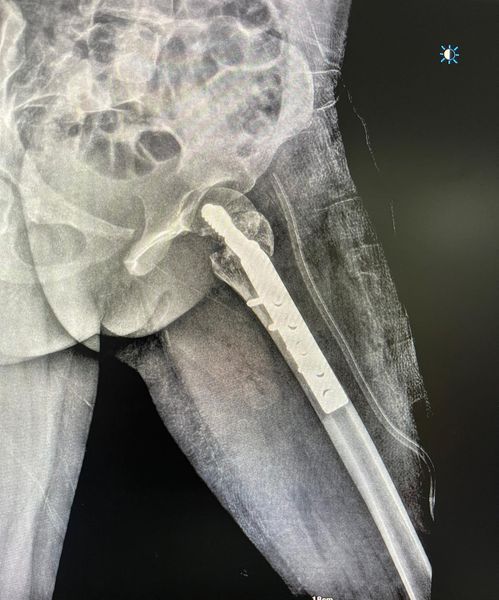

This one was corrected with Pauwel’s osteotomy and pediatric DHS fixation. Cancellous bone grafting was also done to the neck trochanter junction.